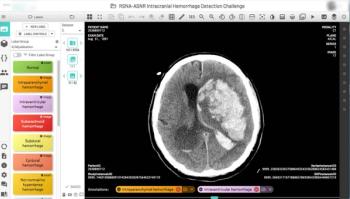

Together, RSNA and the American Society of Neuroradiology launched the largest collection of expert-annotated brain hemorrhage CT scans.